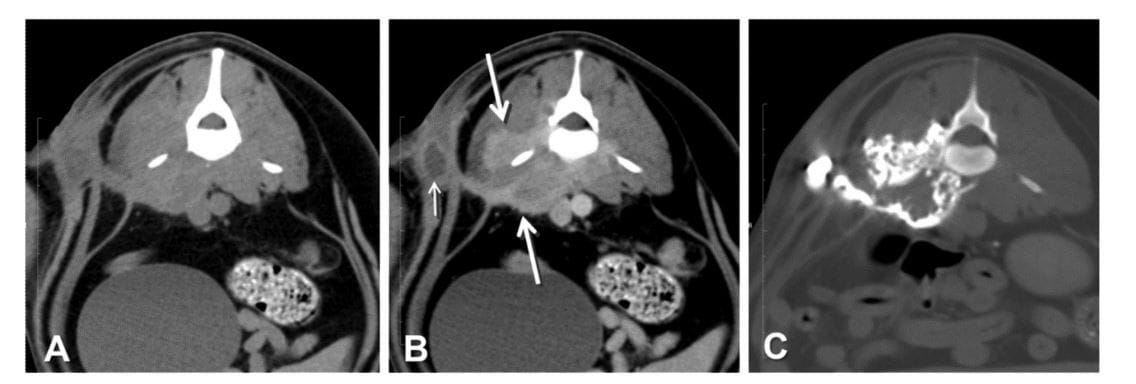

FIG 1. A 3-year old, female, Staffordshire bull terrier dog with history of chronic swelling. Example of CT signs of a flank sinus at the level of L5.

(A) Transverse pre-contrast image. (B) Transverse post-IV contrast image showing a cavitary lesion (small arrow), and swelling and heterogeneous

contrast enhancement of the epaxial and hypaxial muscles (between large arrows); these abnormalities are more clearly visible than in the precontrast image. (C) Transverse sinogram image showing a sinus tract that connects the cavity and muscle lesion; the tracts are more extensive than visualised in A and B